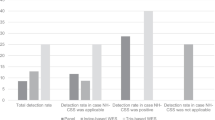

Clinical reports of consecutive patients with a clinical indication of suspected skeletal dysplasia who underwent panel testing were examined. The 543 patients included in the study submitted samples for diagnostic genetic testing with an indication of suspected skeletal dysplasia or growth disorder and received one of three nested panel tests. A molecular diagnosis was established in 42.0% of patients (n = 228/543). Diagnostic variants were identified in 71 genes, nearly half of which (n = 35, 49.3%) contributed uniquely to a molecular diagnosis for a single patient in this cohort. Diagnostic yield was significantly higher among fetal samples (59.0%, n = 52/88) than postnatal samples (38.7%, n = 176/455; z = 3.55, p < 0.001). Diagnostic variants in fetal cases were identified across 18 genes. Thirteen diagnostic CNVs were reported, representing 5.7% of diagnostic findings and ranging in size from 241-bp to whole chromosome aneuploidy. Additionally, 11.4% (36/315) of non-diagnostic patient reports had suspicious variants of unknown significance (VUS), in which additional family studies that provide segregation data and/or functional characterization may result in reclassification to likely pathogenic.

A molecular diagnosis was established in 42.0% of patients (228/543). Diagnostic variants were identified in 71 genes (Fig. 1), with variation in nearly half of these genes (35/71, 49.3%) contributing to a molecular diagnosis for a single patient in this cohort. Overall, the most common genes in which molecular diagnoses were identified included: COL2A1 (n = 36) associated with type II collagenopathies (MIM 120140); FGFR3 (n = 24) associated with achondroplasia, thanatophoric dysplasia, hypochondroplasia, and other conditions such as FGFR-related craniosynostoses (MIM 134934); and COL1A1 (n = 13) or COL1A2 (n = 10) associated with osteogenesis imperfecta (OI; MIM 120150 and 120160, respectively). Together, variation in these four genes accounted for over one third of all molecular diagnoses across the cohort. Among patients with the FGFR3-related molecular diagnoses, four patients with clinical suspicion of achondroplasia (including one fetal case) received a confirmed molecular diagnosis of the FGFR3 NP_000133.1:Gly380Arg variant. Many individuals with clinical suspicion of OI received molecular diagnoses in COL1A1 and COL2A1. However, several patients showed molecular diagnoses in less common OI-related genes. For example, one child had two variants (NM_002615.5: c.271_279dupGCCCTCTCG p.(Ala91_Ser93dup), classified as pathogenic; and c.857_868delTGACCTTGATAG p.(Leu286_Glu290delins*), classified as likely pathogenic) in the SERPINF1 gene, for which gene/pathway-guided treatment may be available. Of note, one heterozygous variant in the difficult-to-sequence exon 12 of the ACAN gene (NM_013227.3), c.5332C > T, p.(Gln1778*), was identified in a child with relative macrocephaly, short stature, hypoplastic chest, bowed forearms, and reduced elbow supination, pronation and extension. Additionally, 11.4% (36/315) of non-diagnostic patient reports had suspicious variants of unknown significance (VUS), including 10 cases in which one pathogenic or likely pathogenic variant and one rare, non-truncating VUS were reported in the same gene in association with an autosomal recessive condition (Additional file 1).

Diagnostic yield was significantly higher among fetal samples (59.0%, n = 52/88) than postnatal samples (38.7%, n = 176/455; z = 3.55, p < 0.001) (Fig. 2). Diagnostic variants in fetal cases were identified across 18 genes (Additional file 2). In addition to disease-causing variation in the FGFR3 (n = 8), COL2A1 (n = 7), COL1A1 (n = 8), and COL1A2 (n = 6) genes, fetal molecular diagnoses were also more common in the DYNC2H1 (n = 3) and SOX9 (n = 3) genes associated with autosomal recessive short-rib thoracic dysplasia (MIM 613091) and campomelic dysplasia (MIM 114290), respectively. Fetal molecular diagnoses were also identified due to variation in the ALPL, COL11A1, COL11A2, CRTAP, ESCO2, EVC2, FGFR2, FLNB, GLI3, RMRP, SLC26A2, and TRIP11 genes.

To our knowledge, this represents one of the largest studies of molecular diagnostics within an unselected population of patients with suspected skeletal dysplasia. The overall diagnostic yield of 42% demonstrates the utility of NGS-based panel testing in identifying molecular diagnoses for individuals with skeletal dysplasia in this cohort. Molecular diagnostic yields can vary substantially based on case selection or study recruitment (including known consanguinity and average age of participants at time of study/clinical ascertainment), effect size of the examined cohort, technical aspects of the genetic testing platforms (such as the inclusion of copy number variant analysis), analysis structure of genetic data (targeted multi-gene vs unbiased exome/genome approach, proband-only vs inclusion of family members for segregation/inheritance analysis), and prior clinical and genetic work-up, among many other factors. Yields tend to be higher in studies with fewer participants, consanguineous populations, cohorts with a younger average age of participants at time of clinical ascertainment, and populations more naïve to prior diagnostic work-up [18]. Both the fetal (58.0%) and postnatal (38.9%) diagnostic yields in this study are consistent with diagnostic yields reported in respective studies of molecular diagnostics among patients with skeletal dysplasia using NGS methods including multi-gene panel testing and exome/genome analysis [15], [2], [17], [13], [16], [14],however, it is important to note that this study characterizes an unselected population with a wide postnatal age distribution and larger number of participants than other published studies. Additionally, the diagnostic yields in these studies such as ours may increase upon continued study of suspicious VUSes. Some of these suspicious VUSs would be reclassified to likely pathogenic if family segregation data showed de novo status for heterozygous variants in genes associated with autosomal dominant conditions, or if variants are confirmed in trans in genes associated with autosomal recessive conditions. Family studies in these cases were not available at the time of analysis but may be pursued later to contribute to evidence supporting variant classification.